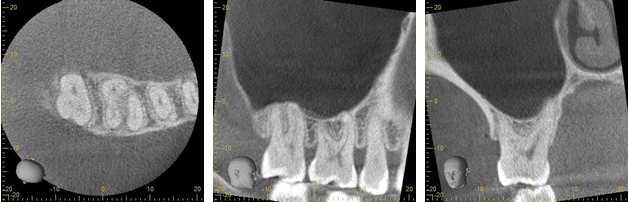

歯科用CT

一般的な歯科用レントゲン画像と比べて歯科用CT画像は上・正面・横から撮影する事が出来ます。

これにより多くの情報を得ることが出来ます。